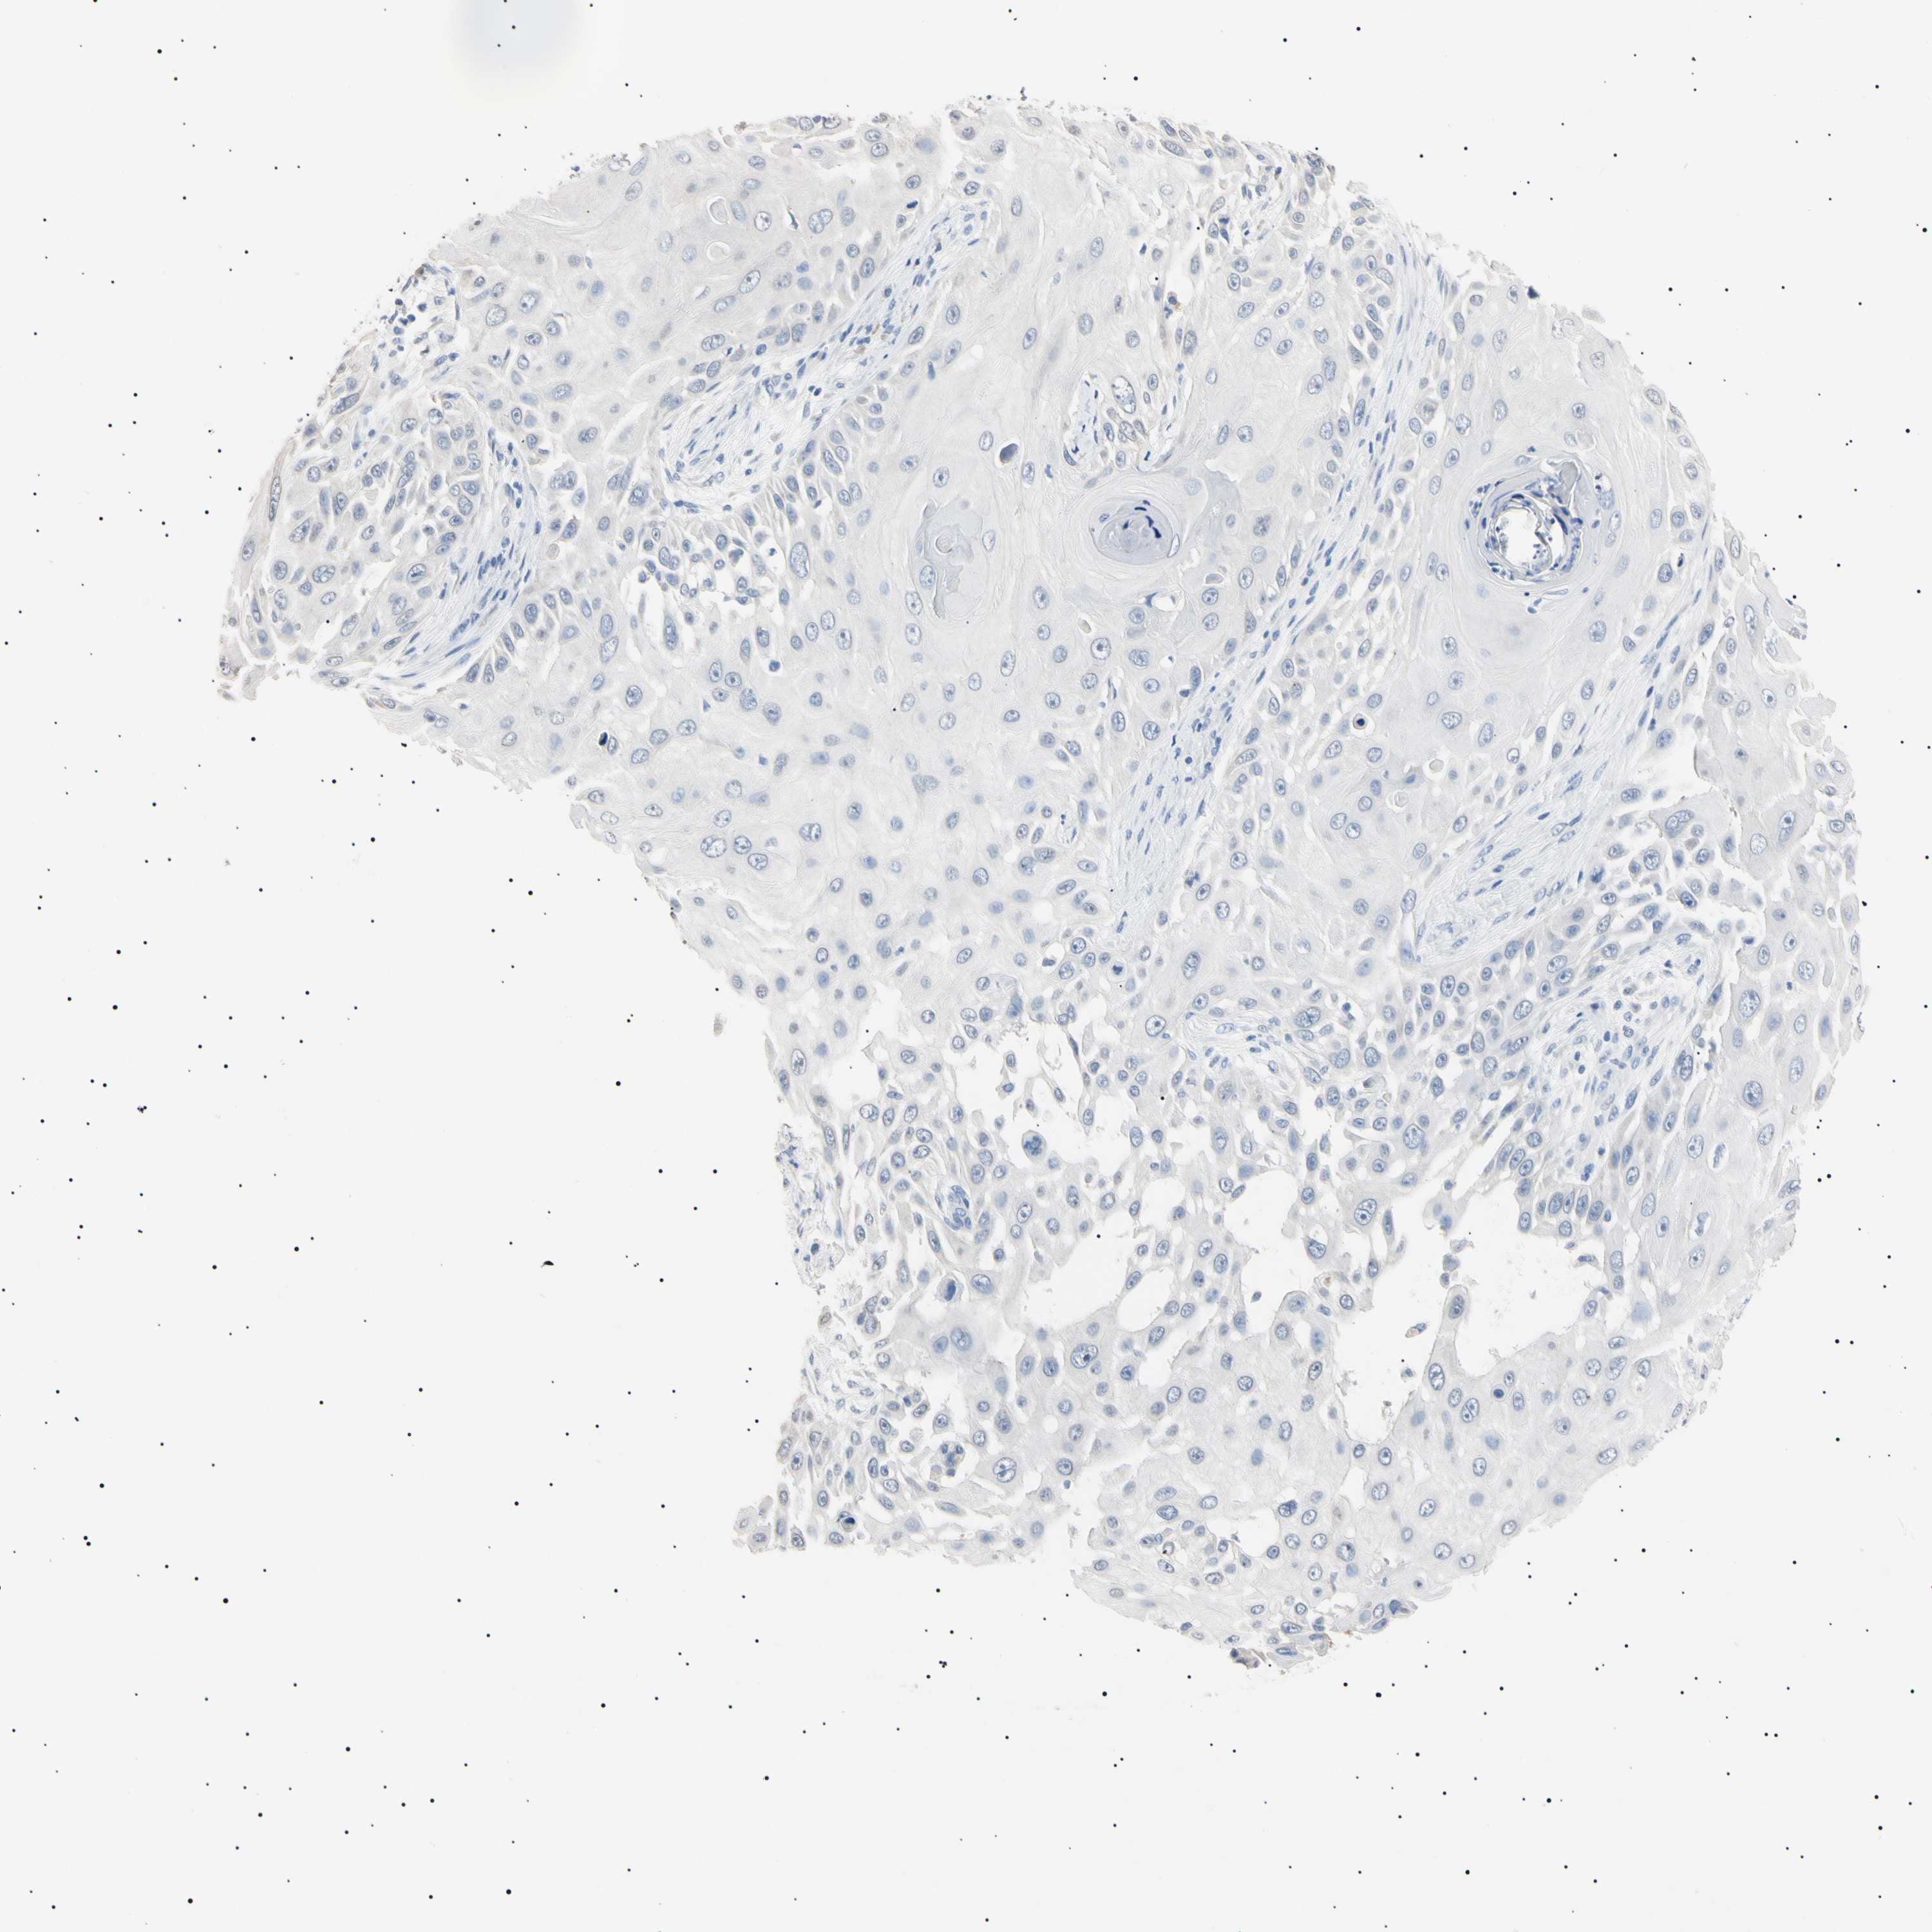

Basal cell and squamous cell cancer

SKIN CANCER - Protein expressioni

A mouse-over function shows sample information and annotation data. Click on an image to view it in a full screen mode. Samples can be filtered based on level of antibody staining by selecting one or several of the following categories: high, medium, low and not detected. The assay and annotation is described here.

Antibody stainingi

Antibody staining in the annotated cell types in the current human tissue is reported as not detected, low, medium, or high, based on conventional immunohistochemistry profiling in selected tissues. This score is based on the combination of the staining intensity and fraction of stained cells.

Each image is clickable and will lead to virtual microscopy that enables deeper exploration of all samples and also displays staining intensity scores, fraction scores and subcellular localization as well as patient and tissue information for each sample.

Antibody HPA038925

Antibody HPA038934

Antibody CAB000042

Antibody CAB010884

Basal cell carcinoma

Squamous cell carcinoma, NOS

Squamous cell carcinoma, metastatic, NOS